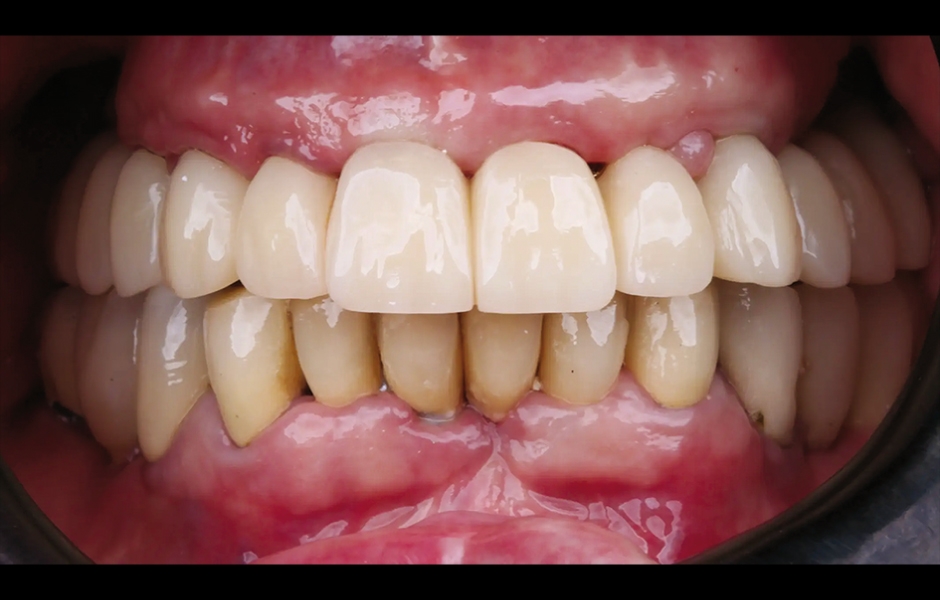

Při finální návštěvě byla nasazena definitivní hybridní šroubem fixovaná protetika. Definitivní práce sestávala z CAD/CAM titanového skeletu přišroubovaného na všechny implantáty a tří monolitických zirkoniových segmentů vlepených nahoře (obr. 18a–c). Byla zkontrolována okluze a pacient byl zařazen do čtyřměsíčního recall programu. Při poslední kontrole (rok po implantaci) byly všechny implantáty úspěšné a pacient byl plně spokojen s novou protetikou (obr. 19–22).

Obr. 19: Definitivní protetická práce při jednoroční kontrole, frontální pohled.